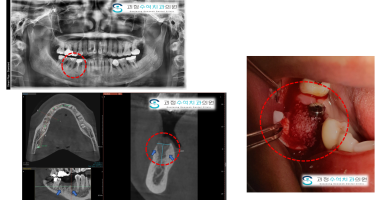

사랑니를 뽑아야하는 이유

보이시나요? 사랑니를 발치해보니 오랜기간 사용해야하는 큰 어금니가 사랑니의 영향으로 흡수가 되었어요....